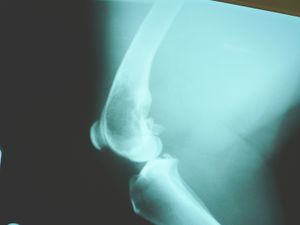

- الأشعة السينية